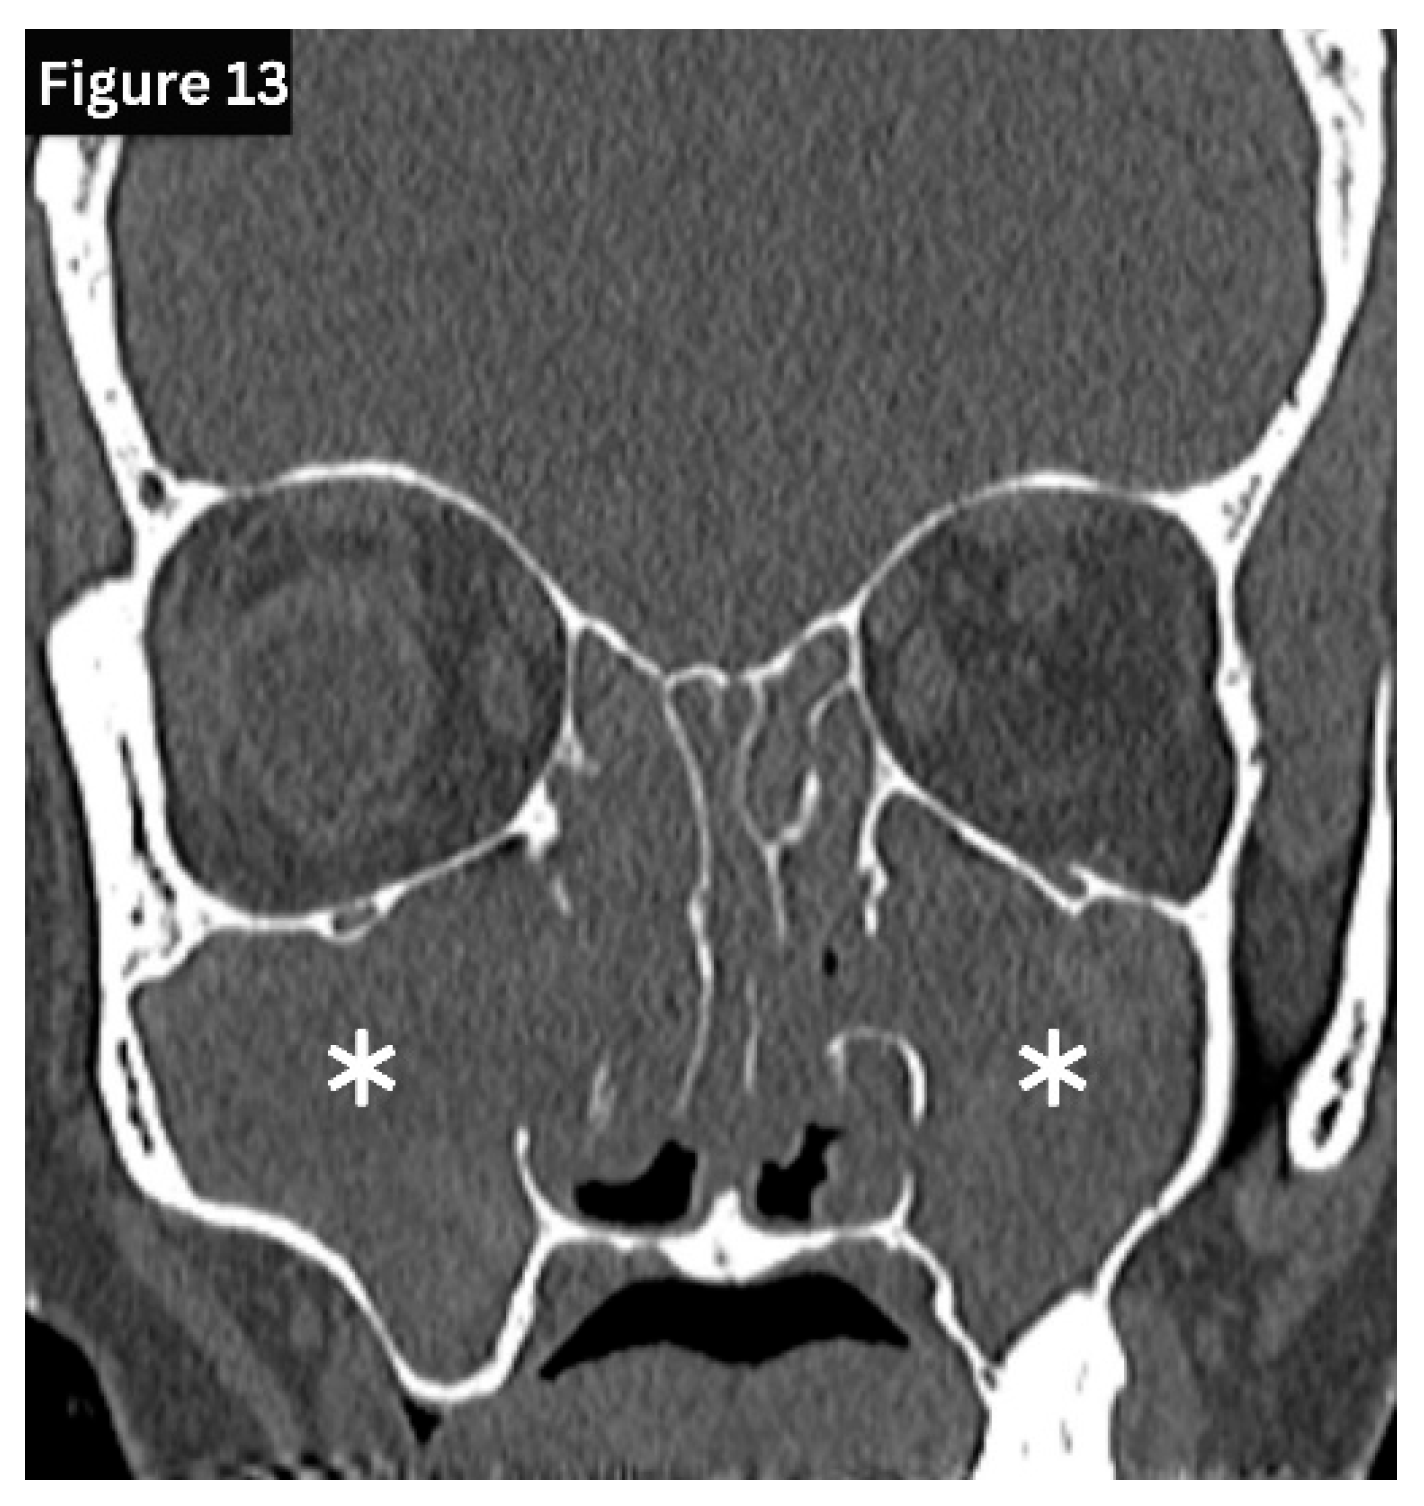

Acute sinusitis typically demonstrates air–fluid levels, diffuse mucosal thickening, and narrowing of the sinus drainage pathways on imaging. (Figure 11) Chronic sinusitis develops over several months and is characterised by persistent polypoid mucosal thickening, bony remodelling, and sclerosis of the sinus walls on sinus HRCT. (Figure 12 and Figure 13) Allergic fungal rhinosinusitis is characterised by expanded sinuses containing centrally hyperdense inspissated mucin, accompanied by a peripheral hypodense mucosal rim, often in association with nasal polyps, as seen on HRCT. Recurrent and subacute sinusitis exhibits overlapping features of both acute and chronic disease. This is often associated with partial ostial obstruction or underlying anatomical variations [5,16].

Figure 13. Coronal CT demonstrates extensive chronic rhinosinusitis with complete opacification of the maxillary and ethmoid sinuses and near-total nasal cavity obliteration.